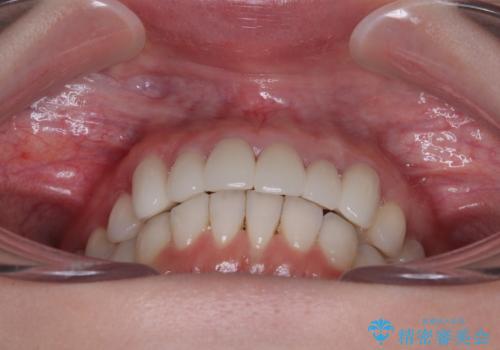

- 全体的なデコボコと、奥歯の欠損を放置した結果倒れ込んだ奥歯などを気にして来院された患者様です。

ワイヤー矯正の方が理想的な仕上がりとできる状態でしたが、上顎前歯にクラウンが装着されているため、インビザラインにて矯正治療を行うこととしました。

インビザラインのみで対応できないときにはワイヤー矯正を併用することとし、矯正治療後にはオールセラミッククラウンによる補綴治療を行うこととしました。

矯正治療自体はインビザラインで満足のいく仕上がりとなりました。

前歯は根管治療が必要となり、元々舌側に入り込んでいた左上2番目の歯は歯周外科処置により歯肉ラインを整えることとしました。

欠損部位は傾斜歯軸を起き上がらせることができたため、オールセラミッククブリッジにて補綴治療を行いました。

全顎的に満足のいく仕上がりとなりました。